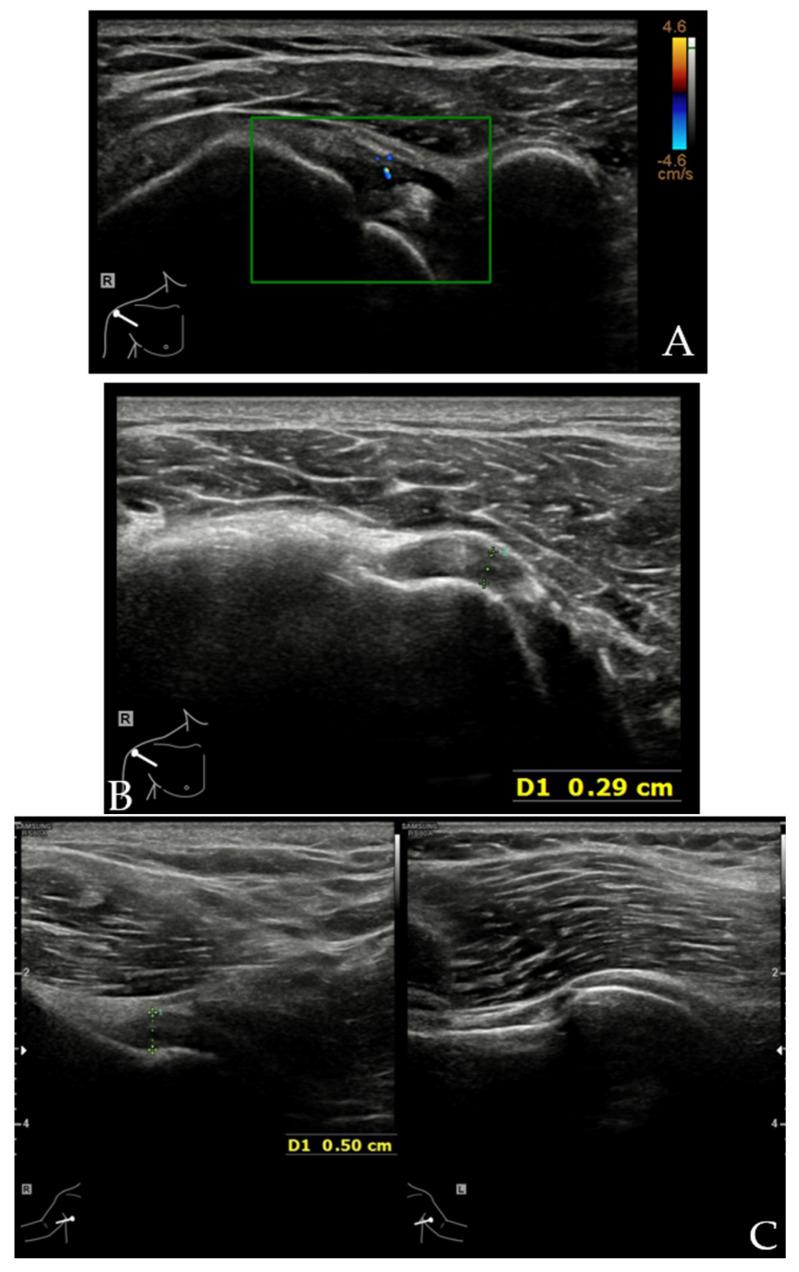

肱二头肌长头肌腱(LHBT)已被公认为是引起肩部前方疼痛的重要原因,会导致肩部屈曲范围显著减小。各种肌腱和韧带结构在LHBT走行过程中形成其锚定装置,以在肩部运动期间维持其适当位置,包括喙肱韧带(CHL)、肩胛上盂肱韧带(SGHL)、肩胛下肌(SSC)肌腱和冈上肌(SSP)肌腱,以及不太为人所知的胸大肌(PM)、背阔肌(LD)和大圆肌(TM)肌腱。该稳定装置的损伤可能导致LHBT不稳定,从而引起肩部前方疼痛。超声检查(US)已越来越多地用于评估肩部损伤,包括LHBT的锚定装置。鉴于解剖结构复杂且病理情况多样,对这些损伤进行准确诊断往往具有挑战性。在这篇综述文章中,将讨论US解剖结构以及影响LHBT锚定装置的常见病理状况,包括肱二头肌滑车损伤、粘连性关节囊炎、SSC和SSP肌腱的慢性病变、PM肌腱撕裂以及LD和TM损伤。了解正常解剖结构、合适的扫描技术以及常见病理状况的US表现是准确诊断的关键。